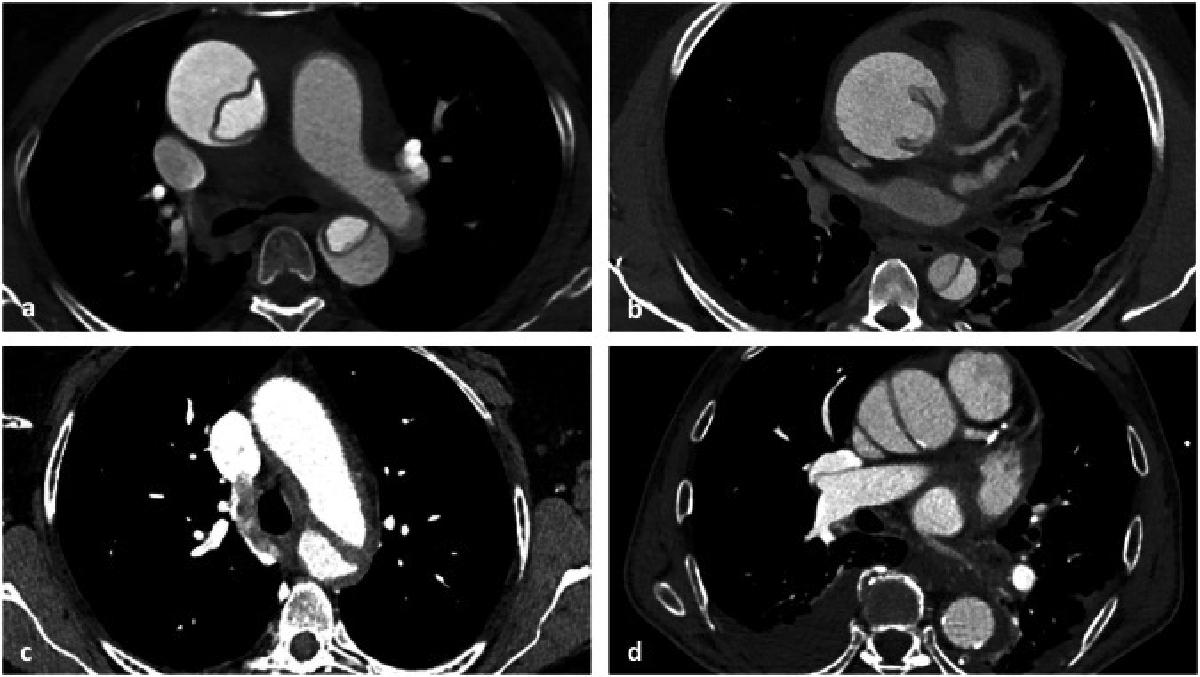

Les dissections aortiques se distinguent en deux catégories. Les dissections de type A, qui touchent l’aorte ascendante, présentent une mortalité immédiate extrêmement élevée, tandis que les dissections de type B, qui concernent l’aorte descendante, longtemps considérées comme moins graves, affichent pourtant une mortalité intrahospitalière d’environ 12 %. « Parmi les formes qui se compliquent, qui représentent un tiers des patients, on atteint des niveaux de mortalité comparables aux dissections de type A », explique Marine Gaudry. À cela s’ajoutent les anévrismes aortiques, dont le risque de rupture expose à une mortalité de l'ordre